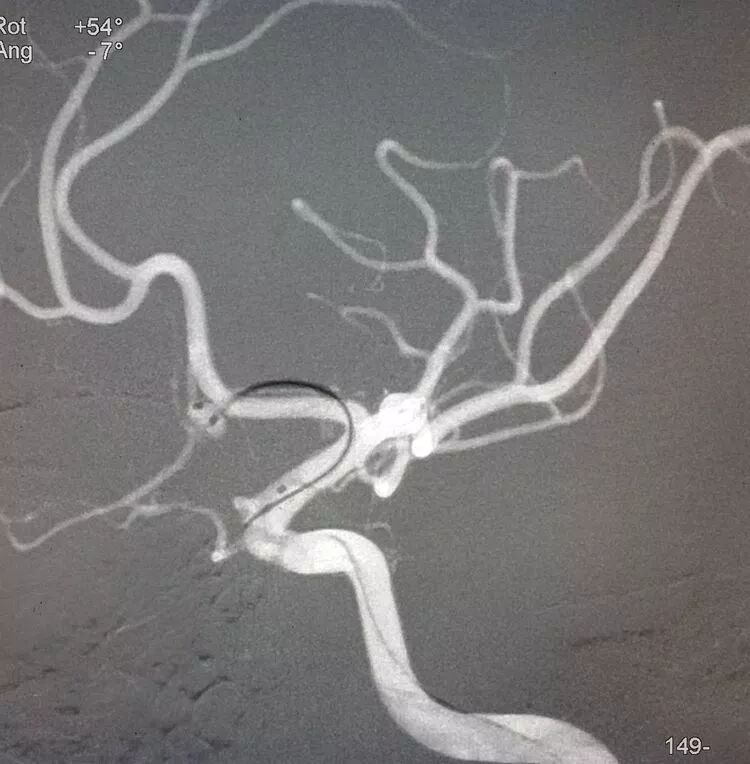

扁平状的前交通动脉瘤

仍然用双微管技术栓塞,一根直头微导管进入瘤体上部,另一根微导管头端塑成C形进入瘤体下部,分区栓塞该瘤